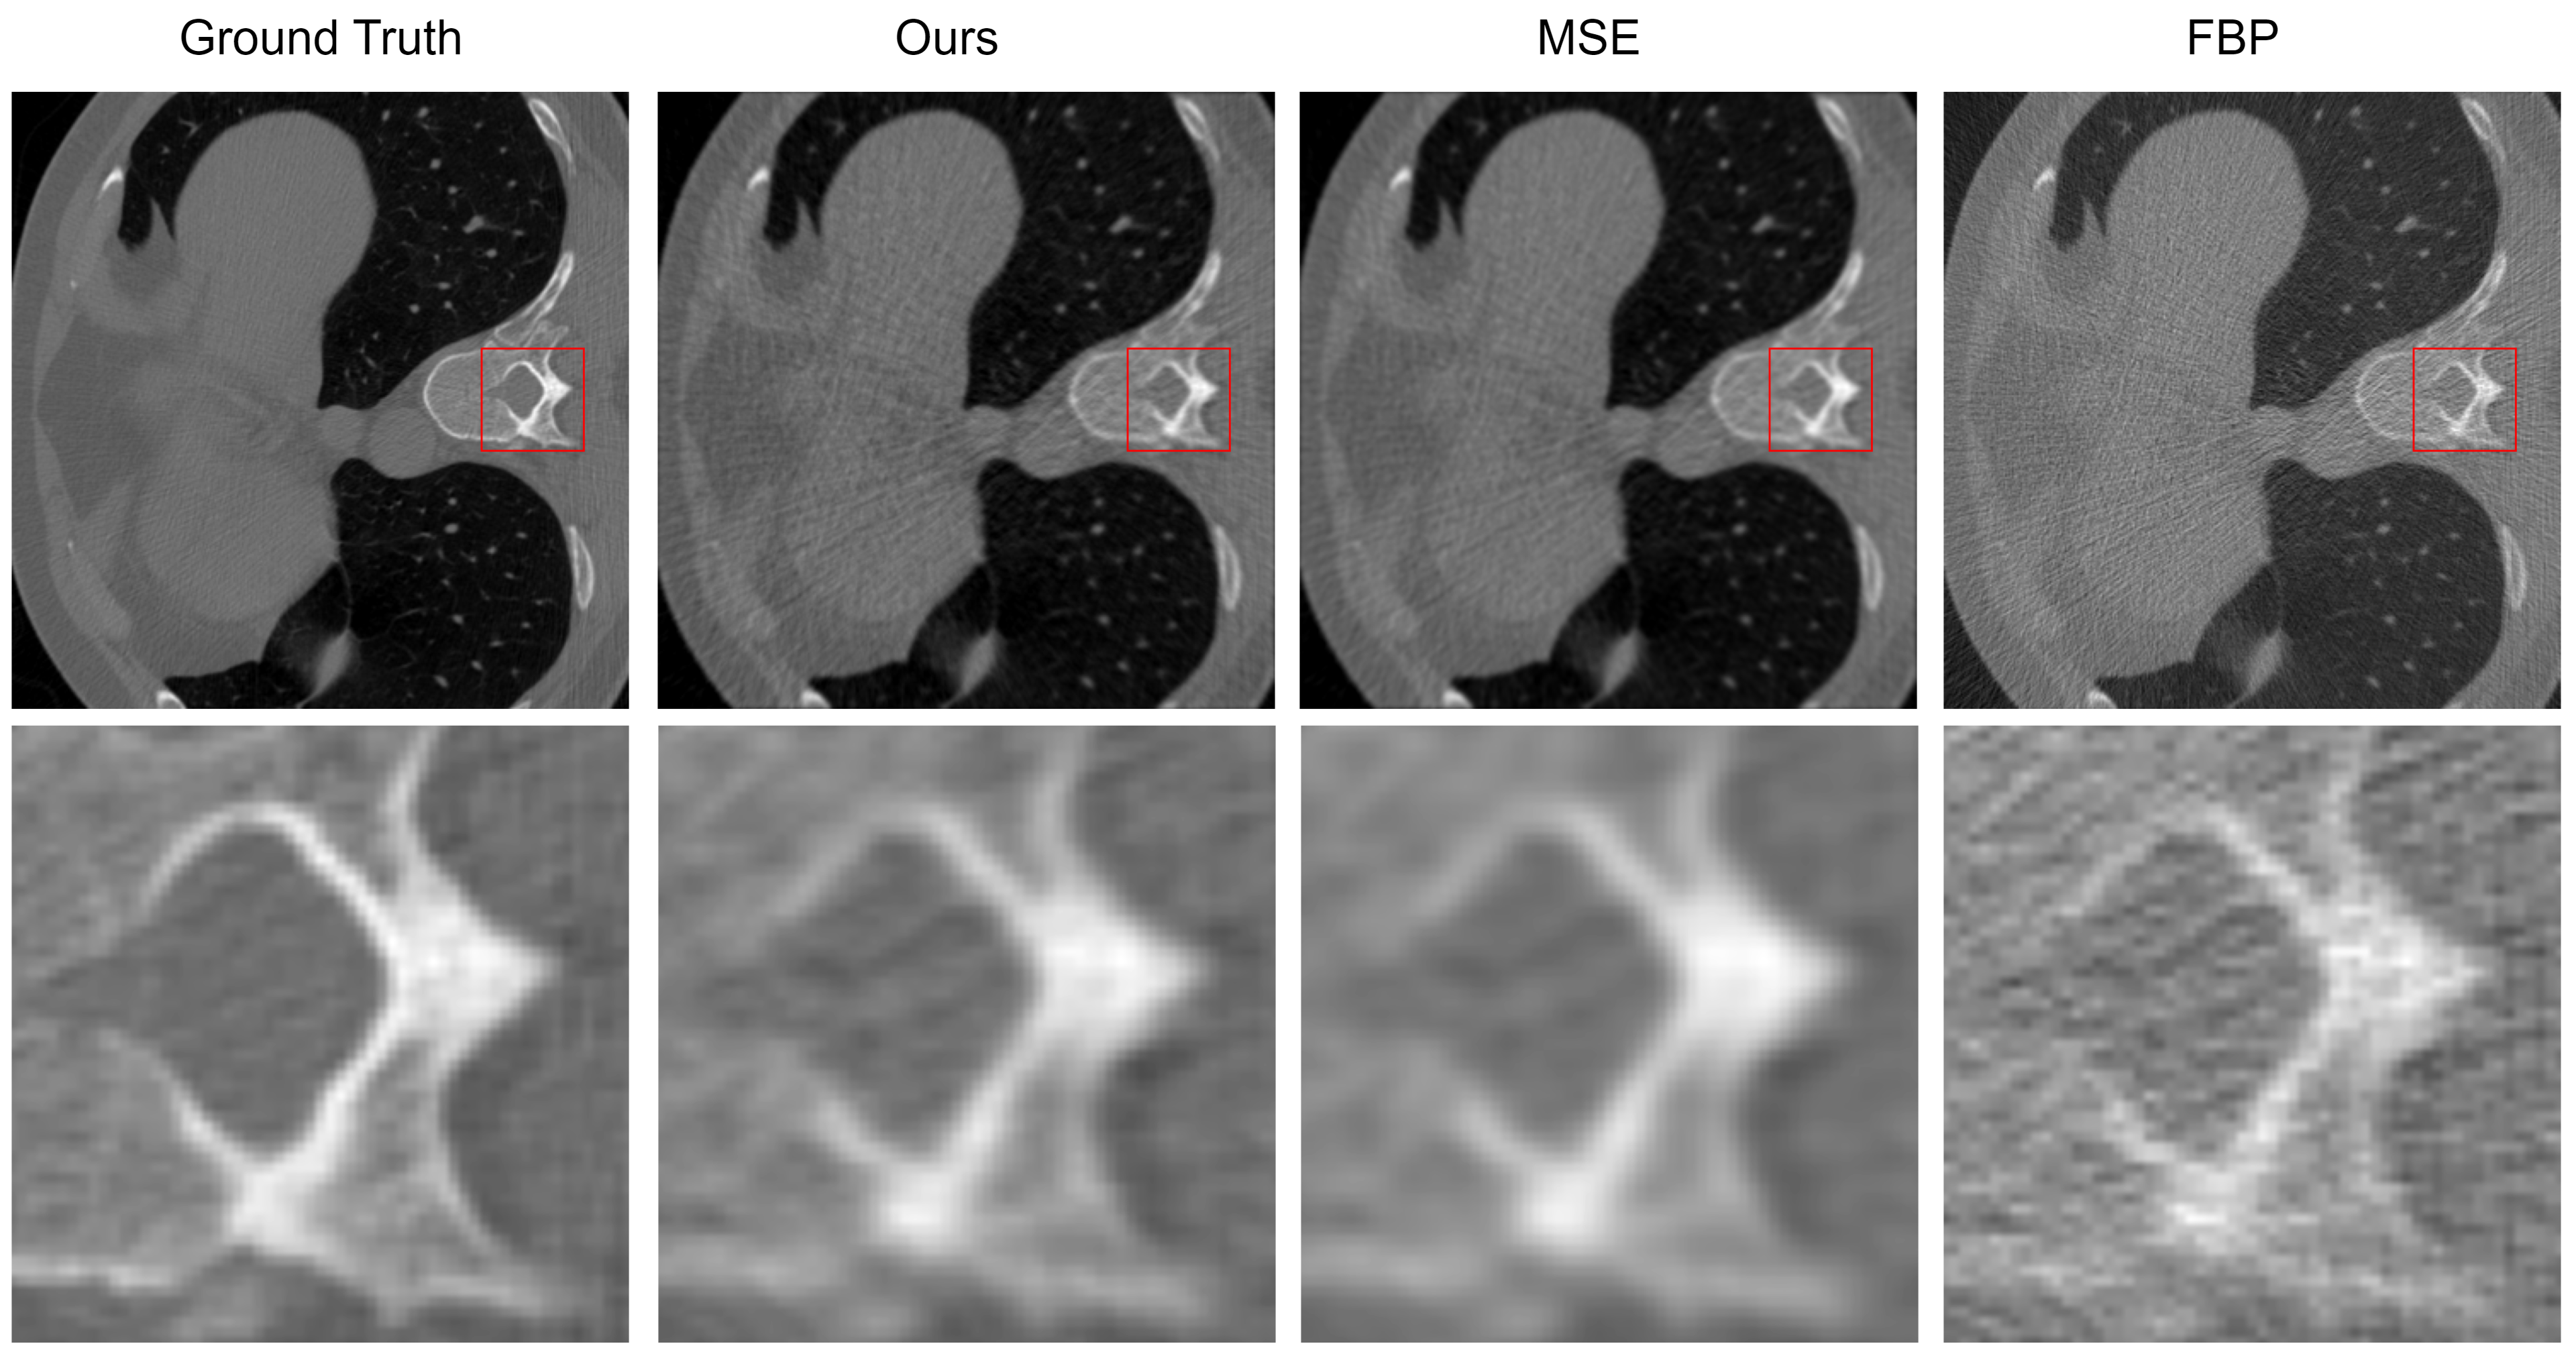

Figure 2 provides a detailed visual comparison of CT image reconstructions utilizing traditional methods such as FBP, MSE optimization, and our proposed method employing a composite loss function. The effectiveness of the reconstruction techniques is particularly observed in high-contrast regions, which are crucial for identifying and evaluating clinical features. Our method’s reconstruction, distinctly visible in the red boxed insets, reveals a significant enhancement in the preservation of geometrical structures, especially evident in the vertebral architecture within the chest CT scans.

Figure 2: Comparative analysis of reconstruction results: When compared to MSE, our composite loss function demonstrates superior detail retention and image sharpness. In comparison to the traditional FBP method, our approach excels in high-frequency noise suppression and provides clearer structural definition.

Delving deeper into the qualitative analysis, Figure 3 employs the Laplace map, a second-order gradient representation that accentuates regions of rapid intensity change, often associated with edges and other structural details in medical images. The bright bands in the Laplace map correlate with edges in the image; narrower bands represent sharper edges. The reconstruction of our model demonstrates narrow bands within the zoomed regions, indicating a preservation of edge sharpness.

Figure 3: Comparison of reconstruction in Laplace map: In contrast to supervised training using MSE, our approach demonstrates superior edge sharpness. When compared to the conventional FBP method, our approach showcases a more distinct edge structure and reduced high-frequency noise.